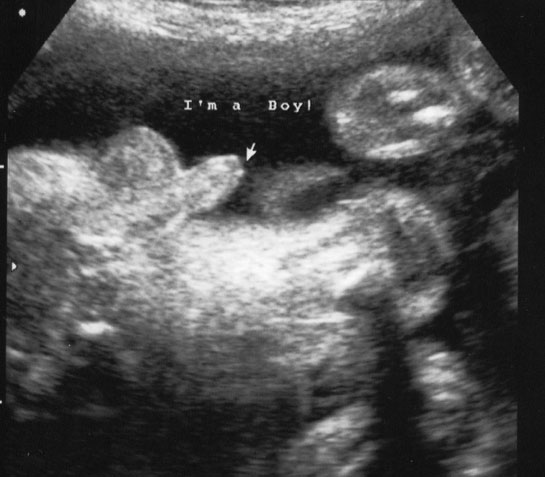

| 36 haftalık gebelik, bir hamilelik sürecinin önemli bir aşamasını temsil eder. Bu dönem, fetüsün gelişiminde kritik bir dönemdir ve anne adayının sağlığı bakımından da dikkate alınması gereken birçok faktör vardır. Bu makalede, 36 haftalık gebelik sürecinin özellikleri, anne adayı ve fetüs üzerindeki etkileri ile birlikte, bu dönemde dikkat edilmesi gereken konular ele alınacaktır. Fetüs Gelişimi 36 haftalık gebelikte fetüs, doğuma oldukça yakın bir dönemde bulunmaktadır. Bu aşamada fetüsün gelişimi ile ilgili bazı önemli noktalar şunlardır: